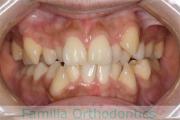

No.23V-478

- 主な症状:

- 叢生

- 年齢:

- 30歳

- 性別:

- 男性

- 抜歯部位

- 上:

- 44済

- 下:

- 8558済

- 主な使用装置:

- FEA 022

- 治療にかかった費用:

- 76万円

右上の歯が重なっているところが邪魔になるとのことで矯正治療を始められた患者さんで、札幌から転院されました。当院で約1年半、15回程度の通院が必要でした。叢生(でこぼこ、凹凸、ガタガタ)が強く、後戻りのリスクが高いケースです。